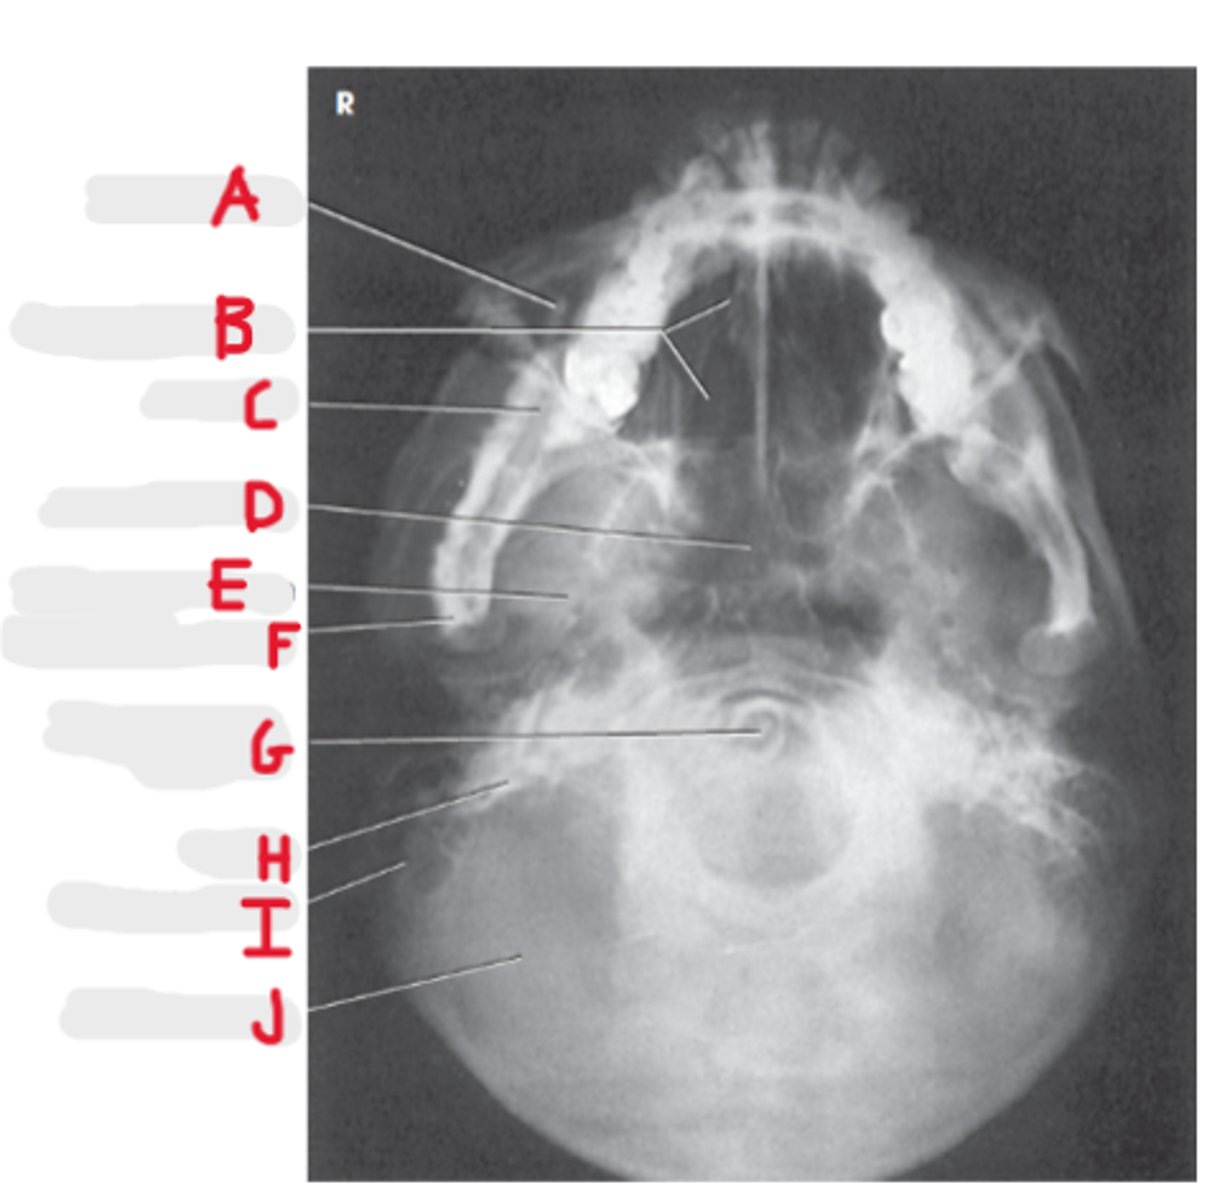

Parietal bone

A

Frontal bone

B

Dorsum sella

C

Supraorbital margin

D

Petrous ridge

E

Crista galli

F

Ethmoidal sinus

G

PA Skull

What projection is this?

Orbits fill the petrous ridges

How can we tell this is a PA skull?

CR to exit the nasion

What is the CR for a PA or PA axial (Caldwell) skull?

OML perpendicular to IR

What line should be perpendicular to the IR for a PA or PA axial (Caldwell) skull?

Frontal sinus

Superior orbital margin

Superior orbital fissure

Ethmoid sinus